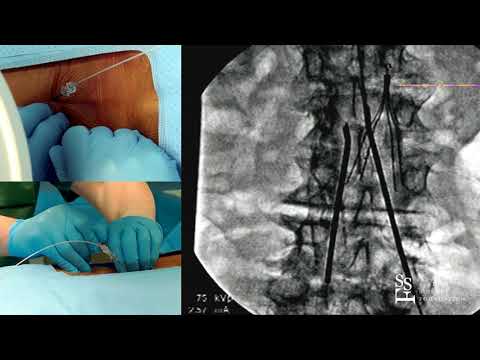

Placing a Spinal Cord Stimulator